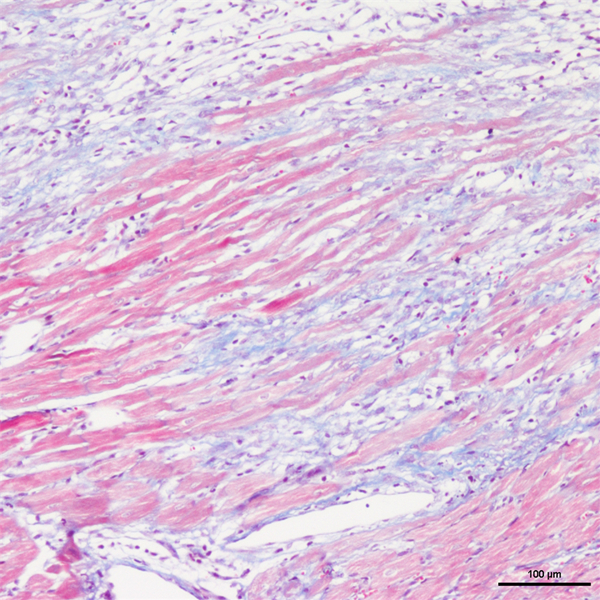

Masson染色(丽春红酸性品红-苯胺蓝染色法)是检测动物组织中胶原纤维的常用染色方法之一。该方法可将胶原纤维染为蓝色,肌纤维与红细胞染为红色,能够有效区分胶原纤维与肌纤维,同时清晰显示各类组织中胶原纤维的含量及纤维化程度。

Masson染色中,胶原纤维可呈现蓝色(被苯胺蓝染色)或绿色(被亮绿染色),肌纤维则呈现红色(被酸性品红、丽春红染色),这一染色差异与阴离子染料分子大小及组织渗透性密切相关。具体而言,若将已固定的组织采用一系列阴离子水溶性染料依次或混合染色,可观察到:红细胞被最小分子的阴离子染料着色,肌纤维与细胞质被中等大小的阴离子染料着色,胶原纤维则被大分子的阴离子染料着色。

四、 实验结果展示